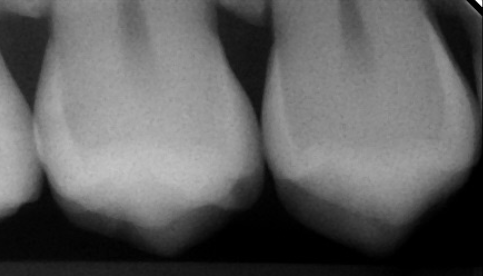

Recent ben ik overgestapt naar een andere tandarts. Bij de nieuwe tandarts blijkt ineens dat ik 6 gaatjes heb, terwijl ik een maand geleden bij mijn vorige tandarts een controle had en daar toen niks aan de hand was. Van deze 6 gaatjes is een vulling die moet worden aangepast en een putje in een kies. Twee andere gaatjes zijn ontstaan onder de vulling. Maar bij de andere twee kiezen kan ik het niet zien. Ik heb hiervan de foto's ontvangen en hij zegt dat daar ook gaatjes in zitten. Maar tussen de twee foto's zie ik geen verschil. Mijn vorige tandarts boort alleen wanneer het echt nodig is en bij de nieuwe krijg ik het gevoel dat die te snel naar de boor krijgt.

Mijn vraag is of er inderdaad gaatjes in deze twee kiezen zitten? En als dit wel het geval is, is het dan nodig om gelijk te boren aangezien er geen verandering is in de afgelopen anderhalf/twee jaar. De eerste foto is ongeveer 1,5/2 jaar geleden gemaakt en andere een week geleden.

Recent ben ik overgestapt naar een andere tandarts. Bij de nieuwe tandarts blijkt ineens dat ik 6 gaatjes heb, terwijl ik een maand geleden bij mijn vorige tandarts een controle had en daar toen niks aan de hand was. Van deze 6 gaatjes is een vulling die moet worden aangepast en een putje in een kies. Twee andere gaatjes zijn ontstaan onder de vulling. Maar bij de andere twee kiezen kan ik het niet zien. Ik heb hiervan de foto's ontvangen en hij zegt dat daar ook gaatjes in zitten. Maar tussen de twee foto's zie ik geen verschil. Mijn vorige tandarts boort alleen wanneer het echt nodig is en bij de nieuwe krijg ik het gevoel dat die te snel naar de boor krijgt.

Mijn vraag is of er inderdaad gaatjes in deze twee kiezen zitten? En als dit wel het geval is, is het dan nodig om gelijk te boren aangezien er geen verandering is in de afgelopen anderhalf/twee jaar. De eerste foto is ongeveer 1,5/2 jaar geleden gemaakt en andere een week geleden.